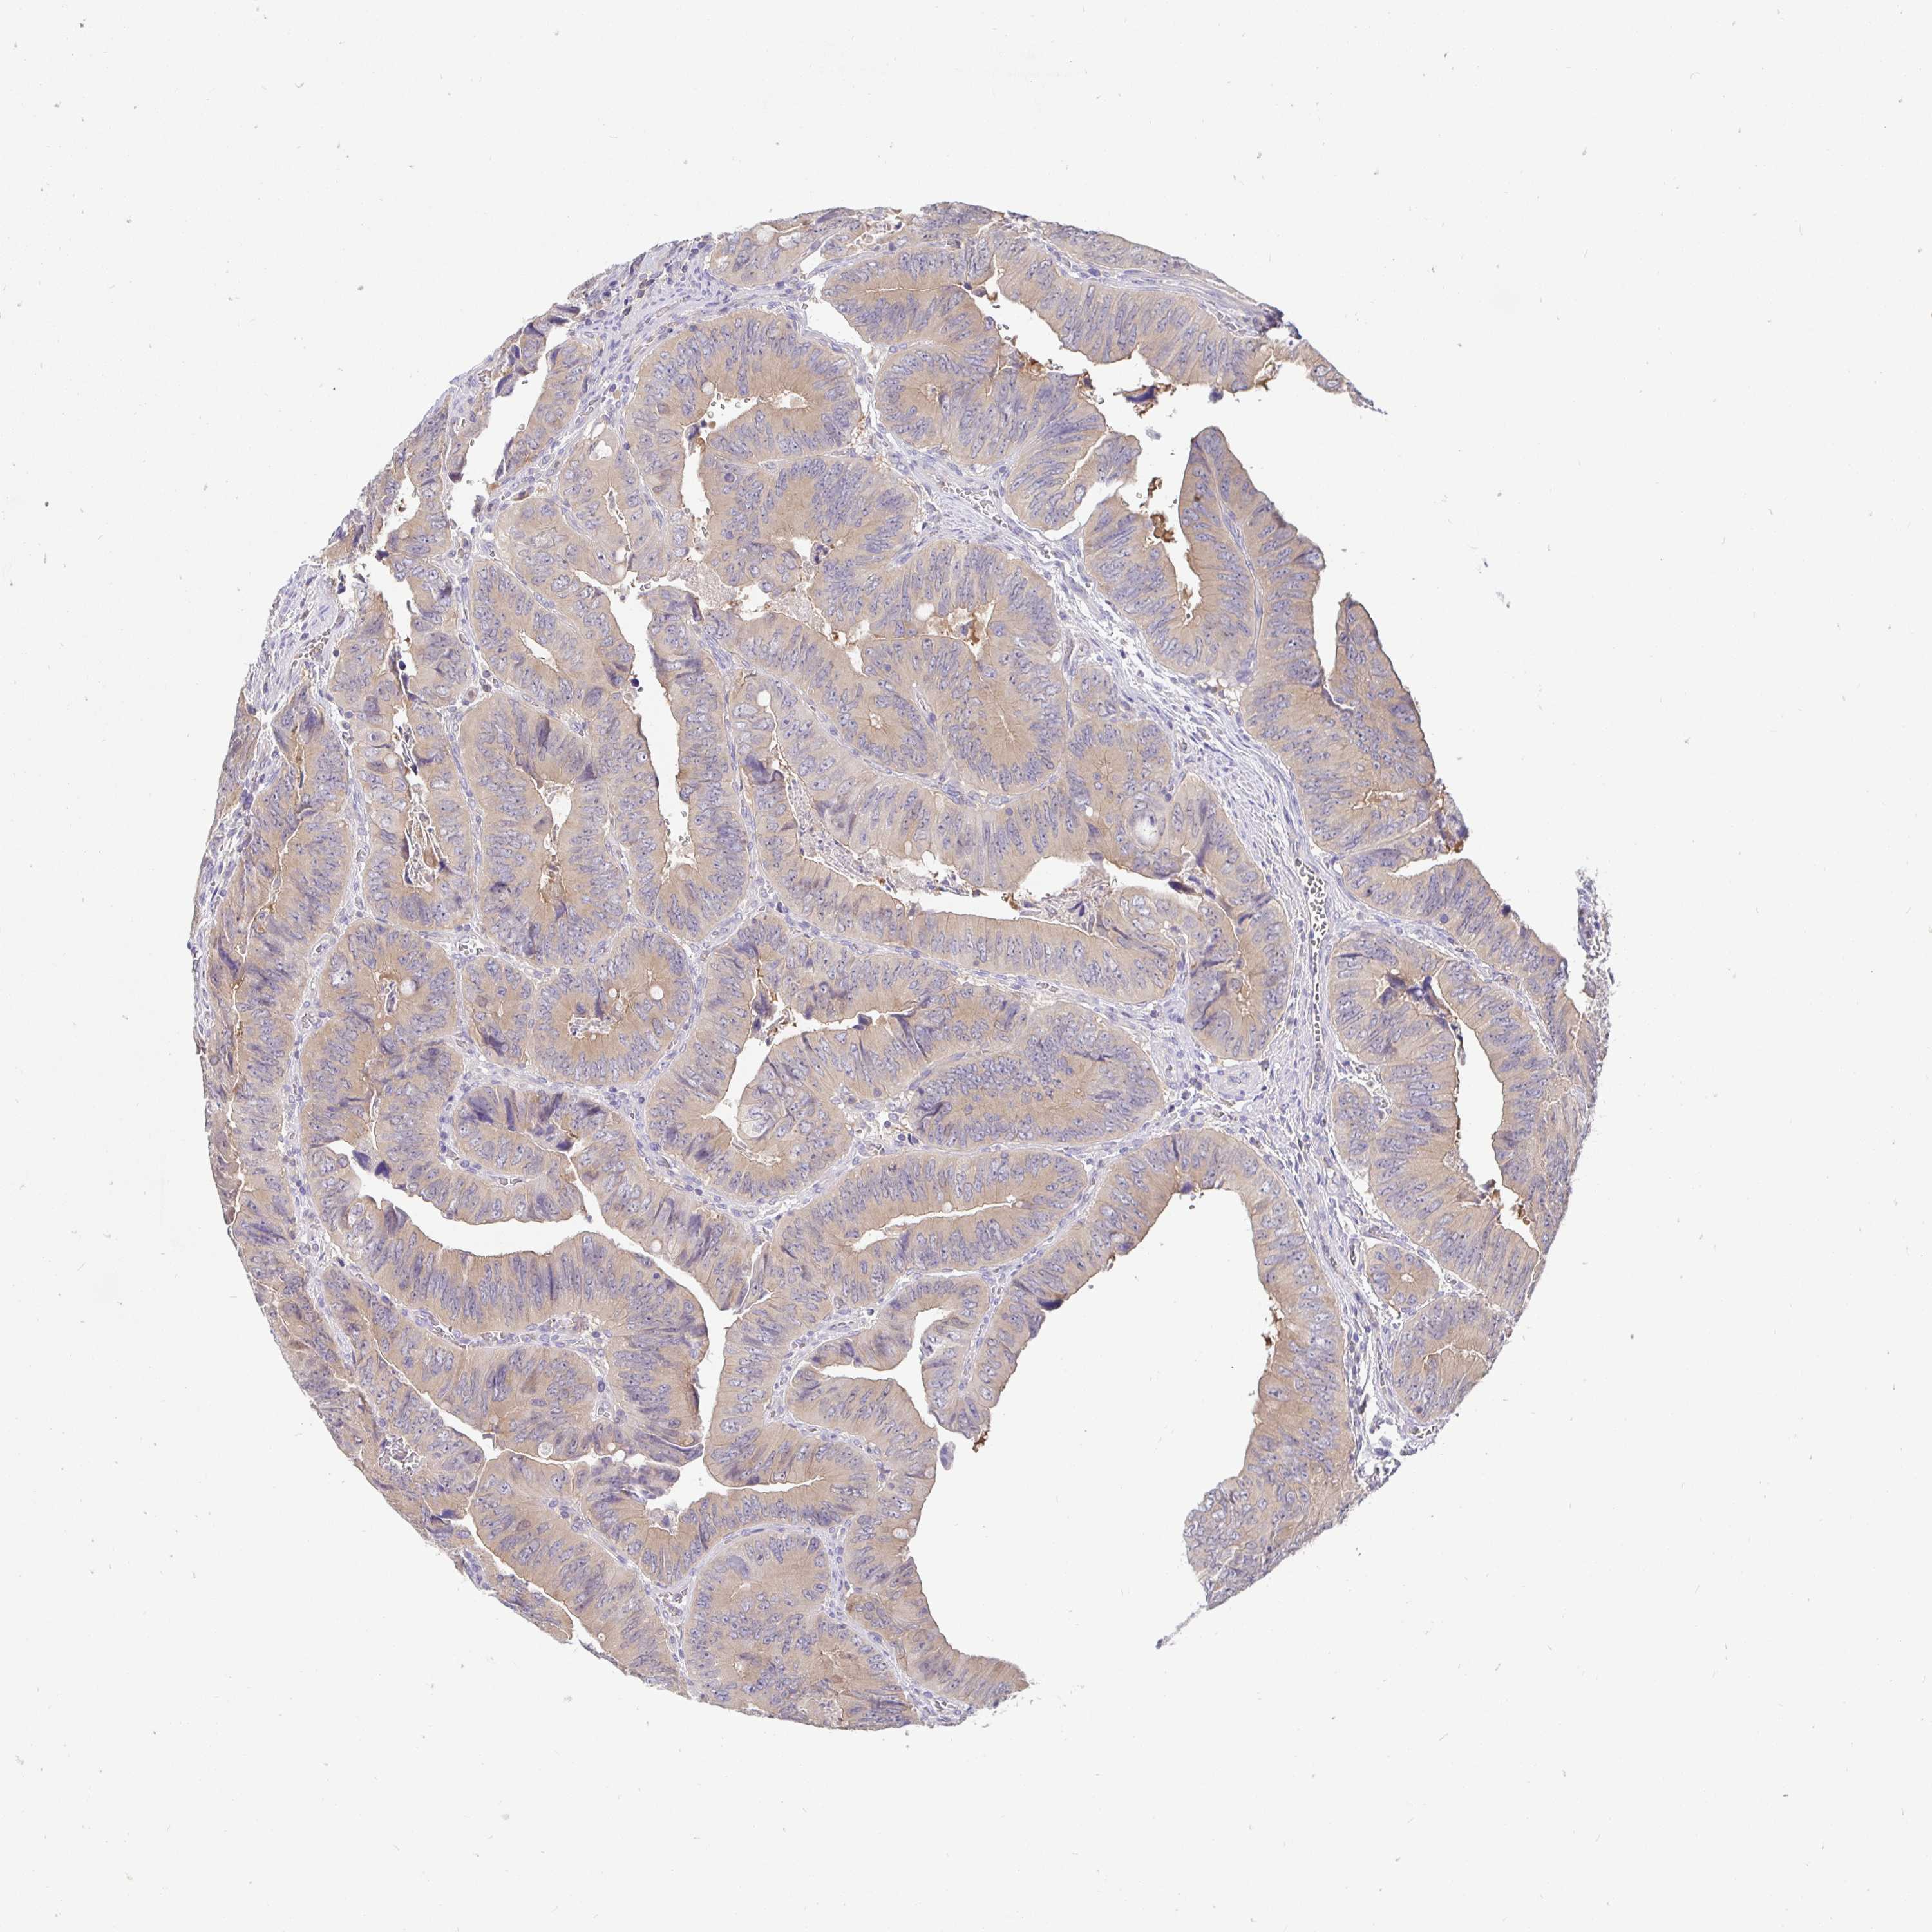

CANCER COLORECTAL CANCER Show tissue menu

Colorectal cancer

Human cancer

Colon adenocarcinoma

RECTUM ADENOCARCINOMA (TCGA) - Interactive survival scatter ploti

KIF21A is not prognostic in Rectum Adenocarcinoma (TCGA)